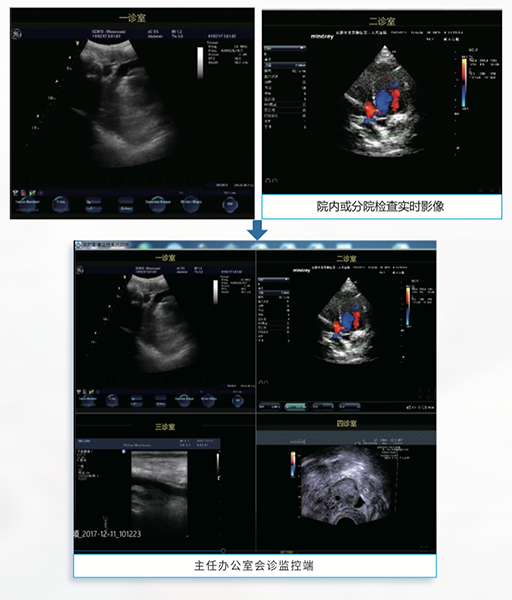

诊间实时影像应用

诊间实时影像应用

上级医生监控